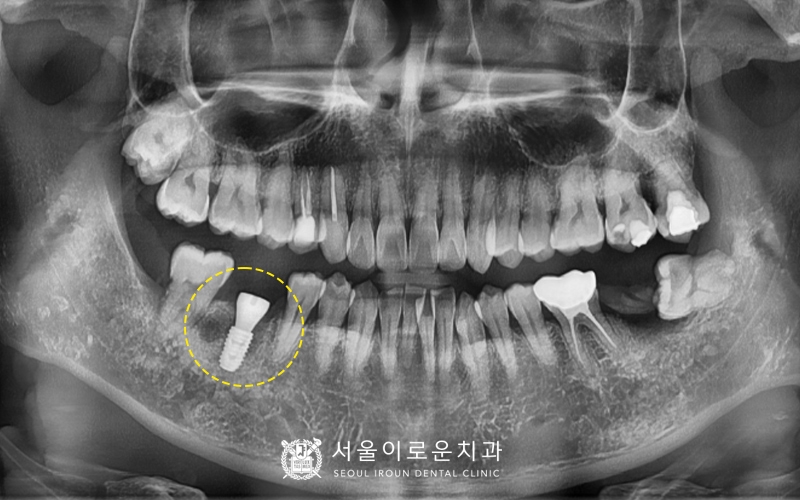

2달반 후

임플란트 픽스처와 잇몸뼈가

잘 붙었는지 확인하기 위해

마찬가지로

osstell beacon 장비를 활용하여

isq 측정한 뒤

안정값을 확인 후 보철과정을 진행하였습니다.

모든치료가 마무리된 뒤

촬영한 x-ray 입니다!